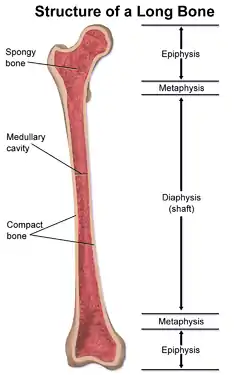

Structure of a long bone, showing the metaphysis | |

The metaphysis is the neck portion of a long bone between the epiphysis and the diaphysis.[1] It contains the growth plate, the part of the bone that grows during childhood, and as it grows it ossifies near the diaphysis and the epiphyses. The metaphysis contains a diverse population of cells including mesenchymal stem cells, which give rise to bone and fat cells, as well as hematopoietic stem cells which give rise to a variety of blood cells as well as bone-destroying cells called osteoclasts. Thus the metaphysis contains a highly metabolic set of tissues including trabecular (spongy) bone, blood vessels , as well as Marrow Adipose Tissue (MAT).

The metaphysis may be divided anatomically into three components based on tissue content: a cartilaginous component (epiphyseal plate), a bony component (metaphysis) and a fibrous component surrounding the periphery of the plate. The growth plate synchronizes chondrogenesis with osteogenesis or interstitial cartilage growth with both appositional bone elongation in conjunction with growth in width, so bearing load and responding to local and systemic forces and factors balance one another mechanically.

During childhood, the growth plate contains the connecting cartilage enabling the bone to grow; at adulthood (between the ages of 18 to 25 years), the components of the growth plate stop growing altogether and completely ossify into solid bone.[2] In an adult, the metaphysis functions to transfer loads from weight-bearing joint surfaces to the diaphysis.[3]